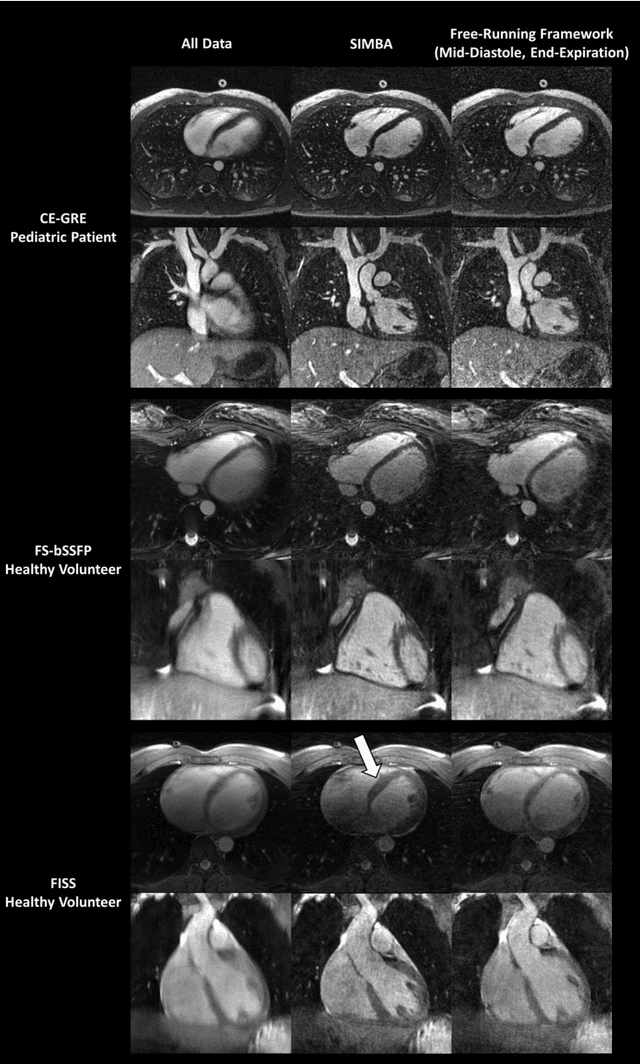

Abstract:Purpose: Whole-heart MRA techniques typically target pre-determined motion states and address cardiac and respiratory dynamics independently. We propose a novel fast reconstruction algorithm, applicable to ungated free-running sequences, that leverages inherent similarities in the acquired data to avoid such physiological constraints. Theory and Methods: The proposed SIMilarity-Based Angiography (SIMBA) method clusters the continuously acquired k-space data in order to find a motion-consistent subset that can be reconstructed into a motion-suppressed whole-heart MRA. Free-running 3D radial datasets from six ferumoxytol-enhanced scans of pediatric cardiac patients and twelve non-contrast scans of healthy volunteers were reconstructed with a non-motion-suppressed regridding of all the acquired data (All Data), our proposed SIMBA method, and a previously published free-running framework (FRF) that uses cardiac and respiratory self-gating and compressed sensing. Images were compared for blood-myocardium interface sharpness, contrast ratio, and visibility of coronary artery ostia. Results: Both the fast SIMBA reconstruction (~20s) and the FRF provided significantly higher blood-myocardium sharpness than All Data (P<0.001). No significant difference was observed among the former two. Significantly higher blood-myocardium contrast ratio was obtained with SIMBA compared to All Data and FRF (P<0.01). More coronary ostia could be visualized with both SIMBA and FRF than with All Data (All Data: 4/36, SIMBA: 30/36, FRF: 33/36, both P<0.001) but no significant difference was found between the first two. Conclusion: The combination of free-running sequences and the fast SIMBA reconstruction, which operates without a priori assumptions related to physiological motion, forms a simple workflow for obtaining whole-heart MRA with sharp anatomical structures.